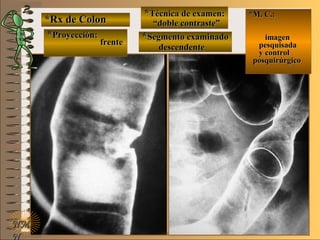

**Segmento examinado:Segmento examinado:

panorámicapanorámica

*M. C.:*M. C.:

sin clínicasin clínica

NMNM

BBAA CC

E ME M

UNTUNT

pacientepaciente

de piede pie

enen

decúbitodecúbito

dorsaldorsal

plieguespliegues

gástricosgástricos

áreasáreas

gástricasgástricas

volvervolver

*Rx de Estómago*Rx de Estómago

**Proyección:Proyección: